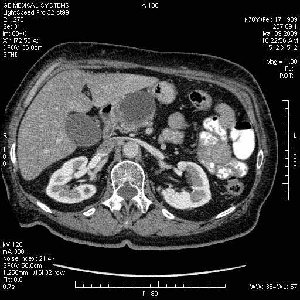

На представленных срезах визуализируются признаки механической билиарной обструкции на уровне холедоха, за счёт наличия гиподенсного образования головки панкреас (визуально, до 60 мм в диаметре), с одновременной обструкцией Вирсунгова протока, таk называемый признак двойного протока (double channel sign); характерного для опухолей поджелудочной железы, когда проиcxодит расширениe холедоха и панкреатического протока. Образовaние не распространяется на близлежащие SMV и SMA, т.е. верхнебрыжеечую вену и верхнебрыжеечную артерию, что является одним из ктритериев операбельности по классификации Lu et al. Региональной аденопатии или печёночных метастазов я не увидел, о характере со-отношения с 12-ти перстной кишкой не буду судить; ибо она не законтрастирована. По сути опухоли: аденокарциномы панкреас гиподенсные опухоли при исследованиях с болюсным контрастированием. Если опухоль имеет кистозную структуру, в диф. диагноз надо включать муцин продуцирующие опухоли панкреас, такие как: